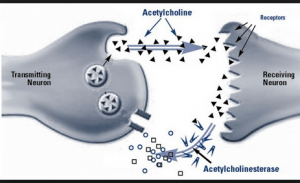

and the LINK to the bio-molecular communications molecule ……ace –> acetylcholine

Acetylcholine – Wikipedia, the free encyclopedia

https://en.wikipedia.org/wiki/Acetylcholine

Wikipedia

Acetylcholine is an organic chemical that functions in the brain and body of many types of animals, including humans, as a neurotransmitter—a chemical …

History · Function · Synthesis and degradation · Receptors

Acetylcholine Neurotransmission (Section 1, Chapter 11 …

neuroscience.uth.tmc.edu › Table of Contents

11.1 Introduction. Acetylcholine, the first neurotransmitter discovered, was originally described as “vagus stuff” by Otto Loewi because of its ability to mimic the …

Acetylcholine – Neuroscience – NCBI Bookshelf

www.ncbi.nlm.nih.gov › … › Bookshelf

National Center for Biotechnology Information

by D Purves – 2001

Acetylcholine is the neurotransmitter at neuromuscular junctions, at synapses in the ganglia of the visceral motor system, and at a variety of sites within the …

Choline transporter —> newspaper messages via –> Cho + line –> Mr. Cho an English major and Virginia tech and his line(s) …. choline messages

Acetylcholine – Wikipedia, the free encyclopedia

https://en.wikipedia.org/wiki/Acetylcholine

Wikipedia

Acetylcholine is an organic chemical that functions in the brain and body of many types of ….. The enzyme acetylcholinesterase converts acetylcholine into the inactive metabolites choline andacetate. This enzyme is abundant in the synaptic …

acetylcholinesterase converts acetylcholine into the inactive metabolites choline and acetate.

Thus ….above we show the ace –> acetylcholine information expression string …. in the EXTERNAL world ..using the EARTH geography surface as an information display screen … like a movie projector.

Thus ….above we show the ace –> acetylcholine information expression string …. in the EXTERNAL world ..using the EARTH geography surface as an information display screen … like a movie projector ….giving…

.the ace –> acetylcholine information expression string …. in the EXTERNAL world ..using the EARTH geography surface as an information display screen …